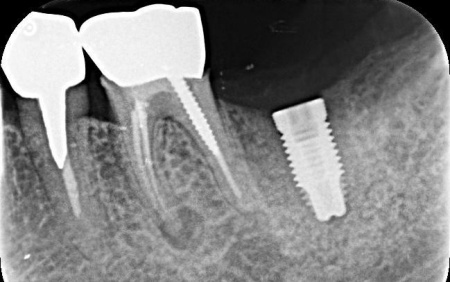

レントゲン撮影を行って詳しく調べたところ、歯根が縦方向に割れている「歯根破折」が疑われる状態です。

その後、歯科用CT撮影を行い、顎の骨の量や形、神経や血管の位置を立体的に確認しました。撮影したデータをもとに、インプラントを埋め込む位置や角度、深さについて事前に設計を行い、安全性と噛み合わせのバランスを考慮した治療計画を立てます。

抜歯後の骨の状態を確認しています。

インプラント体と骨の結合を確認しました。